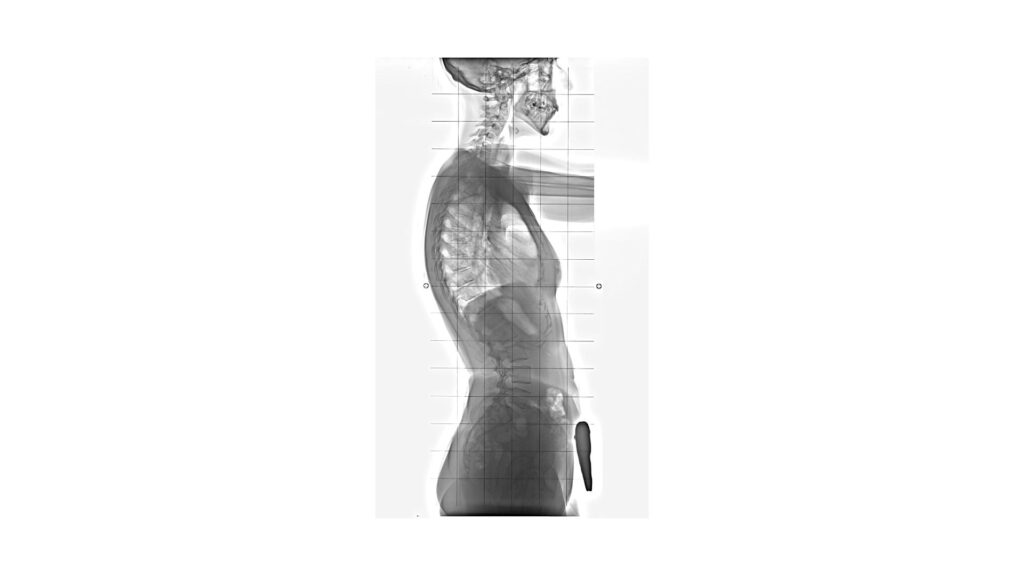

Kręgosłup człowieka nie jest prostą linią – posiada naturalne krzywizny, które pełnią ważną funkcję biomechaniczną. W odcinku szyjnym i lędźwiowym występuje lordoza – wygięcie kręgosłupa do przodu (brzusznie). Dzięki tym krzywiznom kręgosłup działa jak sprężyna, która amortyzuje obciążenia podczas chodzenia, biegania czy skakania.Zatem sama obecność lordozy jest prawidłowa i fizjologiczna.

Kręgosłup to system naczyń połączonych – zmiana jednej krzywizny wpływa na inne. Hiperlordoza lędźwiowa często idzie w parze z hiperkifozą piersiową (czyli zaokrągleniem górnych pleców), a także z wysunięciem głowy do przodu. Takie zaburzenia wpływają na postawę całego ciała, sposób oddychania, a nawet funkcjonowanie narządów wewnętrznych. Dlatego terapia powinna zawsze obejmować całościową analizę postawy, a nie skupiać się tylko na jednym odcinku.